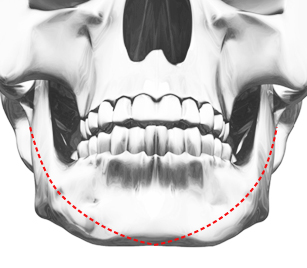

포에버 사각턱성형방법

수술 전

수술 전 -

이중턱, 이차각

가능성을 최소화한

매끈한 얼굴라인 완성

과대한 뼈 절제가 아닌 필요한 만큼만 절제하여

이중턱, 이차각 등의 안면윤곽 부작용 가능성을 최소화 했어요!